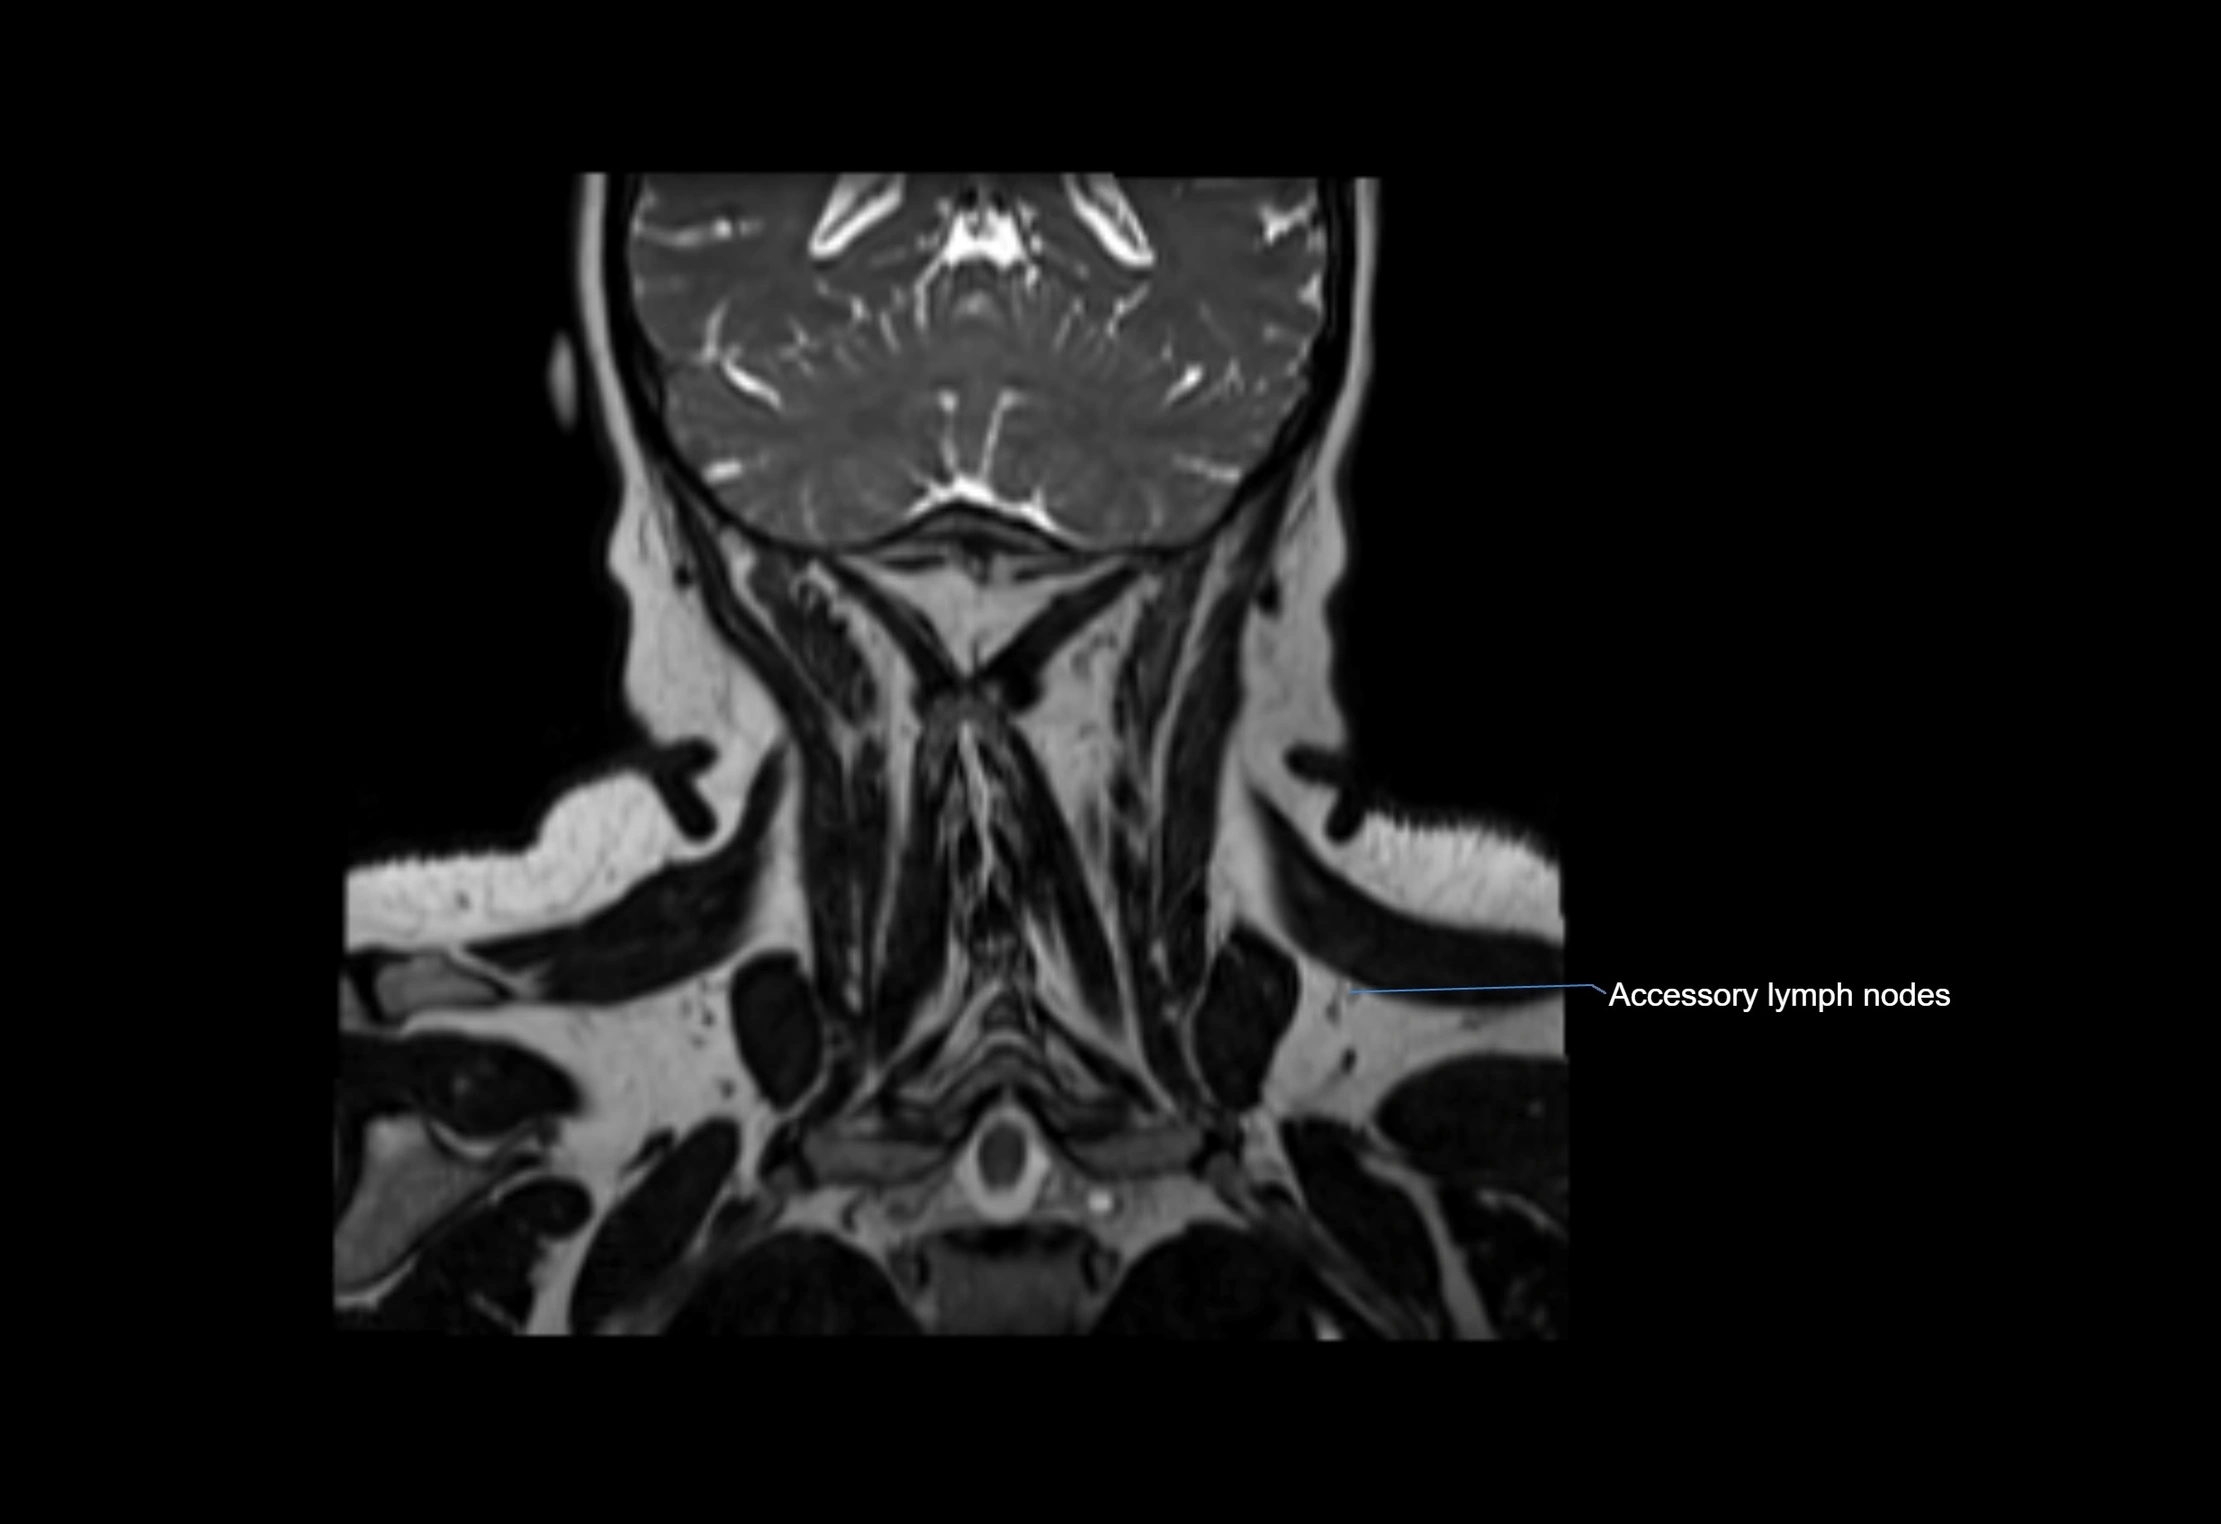

Accessory lymph nodes

Accessory lymph nodes are small, secondary lymph nodes located along the main facial and cervical lymphatic chains, often adjacent to primary lymph nodes, such as preauricular, submandibular, or occipital nodes. They are typically less than 5 mm in diameter, embedded within subcutaneous fat or connective tissue, and may be variable in number and location. These nodes provide additional filtration and immune surveillance for lymph collected from the face, scalp, and neck regions. Accessory lymph nodes are usually non-palpable in healthy individuals but may enlarge in response to infection, inflammation, or metastasis, making them clinically significant.

Location

• Found along primary lymph node chains, including preauricular, submandibular, parotid, and occipital regions

• Embedded in subcutaneous fat or superficial fascia, often lateral or posterior to primary nodes

• Variable in number; may occur unilaterally or bilaterally, depending on individual anatomy

MRI Appearance

T1-weighted images:

• Normal accessory nodes appear as small, oval hypointense to intermediate signal structures within subcutaneous fat

• Surrounded by hyperintense fat, enhancing contrast for visualization

• Pathological nodes may appear enlarged or rounded, sometimes with cortical thickening

MRI images

image